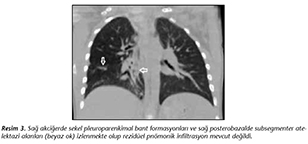

Hastaya uygulanan tedavi işitme testi ve g�rme muayenesi yapılarak amikasin, moksifloksasin, para-amino salisilik asit, protionamid ve pirazinamid� şeklinde değiştirildi. Oral olarak verilen ila�ların miktarının� fazla olması nedeni ile hastaya ila� i�irmekte g��l�kler yaşandı. İla�lar enjekt�rle sulandırarak, ilk haftalarda nazogastrik yol ile devamında hastanın kendisinin ağızdan alımı ile sağlandı. Bu d�nemde oral ila�ları i�mede teşvik edici olsa da nazogastrik sonda �ıkarılarak takip eden g�nlerde izlemde kaşık, enjekt�r, kap gibi malzemeler kullanılarak d�n�ş�ml� olarak ila�ların i�ilmesi sağlandı. Antibiyotik tedavisine her g�n intramusk�ler uygulama şeklinde başlandı. Hasta tedavinin 44. g�n�ne kadar hastanede yatırılarak izlendikten sonra, yaşadığı yerdeki verem savaş dispanseri ile iletişime ge�ilerek ila� temini sağlandı ve ayaktan izleme alındı. Tedavinin 3. ayında kontrol olarak alınan AMS �rneğinde Bactec MGIT 960 ve L�wenstein-Jensen besiyerlerinde �reme olması nedeniyle mevcut tedaviye devam edildi. Amikasin tedavisi 6 aya tamamlandı. Tedavinin son 3 ayında hastanın enjeksiyon yerlerinde ağrı, bacağının �zerine basamama gibi yakınmaları olması nedeni ile haftada 3 g�n olacak şekilde antibiyotik tedavisi 6 aya tamamlandı. Aylık kontrollerine devam edilen hastanın aralıklı olarak bakılan biyokimyasal testleri, tiroid fonksiyonları, g�rme ve işitme muayenelerinde anormallik saptanmadı. Tedavinin 18. ayında yapılan kontrol g�r�nt�lemesinde sekel lezyonlar ile uyumlu� olması, kontrol olarak alınan son 5 AMS �rneğinde �reme olmaması nedeni ile tedavi 24 aya tamamlanarak kesildi (Resim 3).